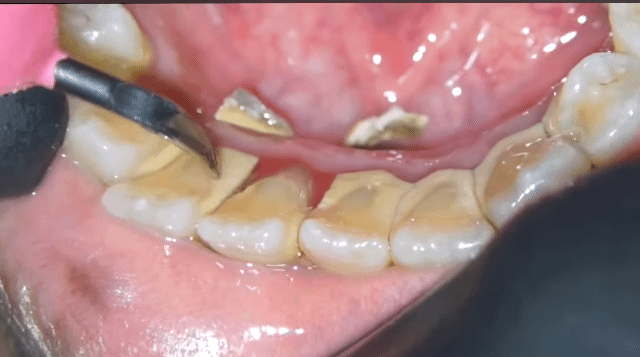

[스크랩] [흥미돋]■ 치과 스케일링 ( 치석 제거)

• 답댓글 작성자야구좋아 | 작성시간 25.03.13 까맣쿤 아니? 아닌 거 같던데! 치석 떼고 나면 잇몸이 부어있어서 그런 욱신거리는 통증?은 조금 있을 수 있어도 치석 많아서 스케일링 할 때 더 아프다는 얘기는 첨 들어봐! 보통 다 못느껴! 치석이 뭉탱이로 떨어지면 그거 막 혀에 닿거나 목구멍에 닿아서 케곅 거리는 사람은 있어...

• 작성자한능검타파 | 작성시간 25.03.13 아 재밌어보이는데... 너무 심하셔서 ㅠ 뿌리가 보일거같아서 안타깝ㅜ

• 작성자박용희 | 작성시간 25.03.13 저정도면 진짜.. 이가 반 정도 빠진만큼 아프겄어

• 작성자촥촥한딸기케이크 | 작성시간 25.03.13 저만큼 쌓일려면 얼마나 안한거야